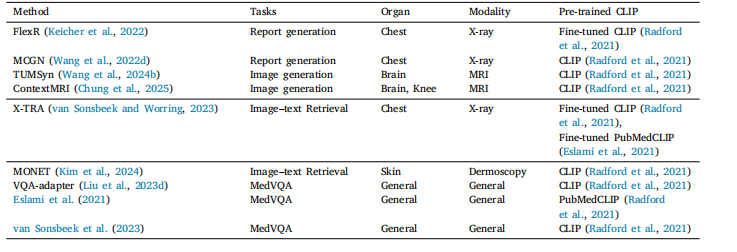

Table 5Overview of representative cross-modality applications

表5 代表性跨模态应用概述。